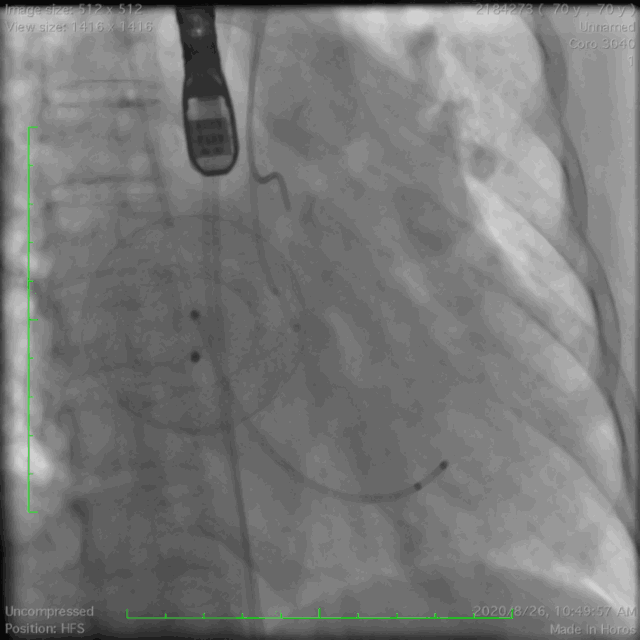

● 手术过程

主动脉根部造影